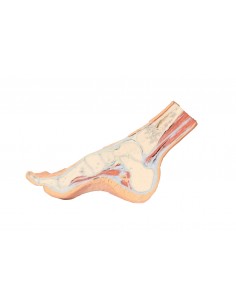

3D Anatomy 1.0 - Extremidades inferiores

Disección transversal parasagital del pie Erler Zimmer 3D anatomy Series MP1850

3D Anatomy 1.0 - Extremidades inferiores

Estructuras de la superficie plantar del pie Erler Zimmer 3D anatomy Series MP1900